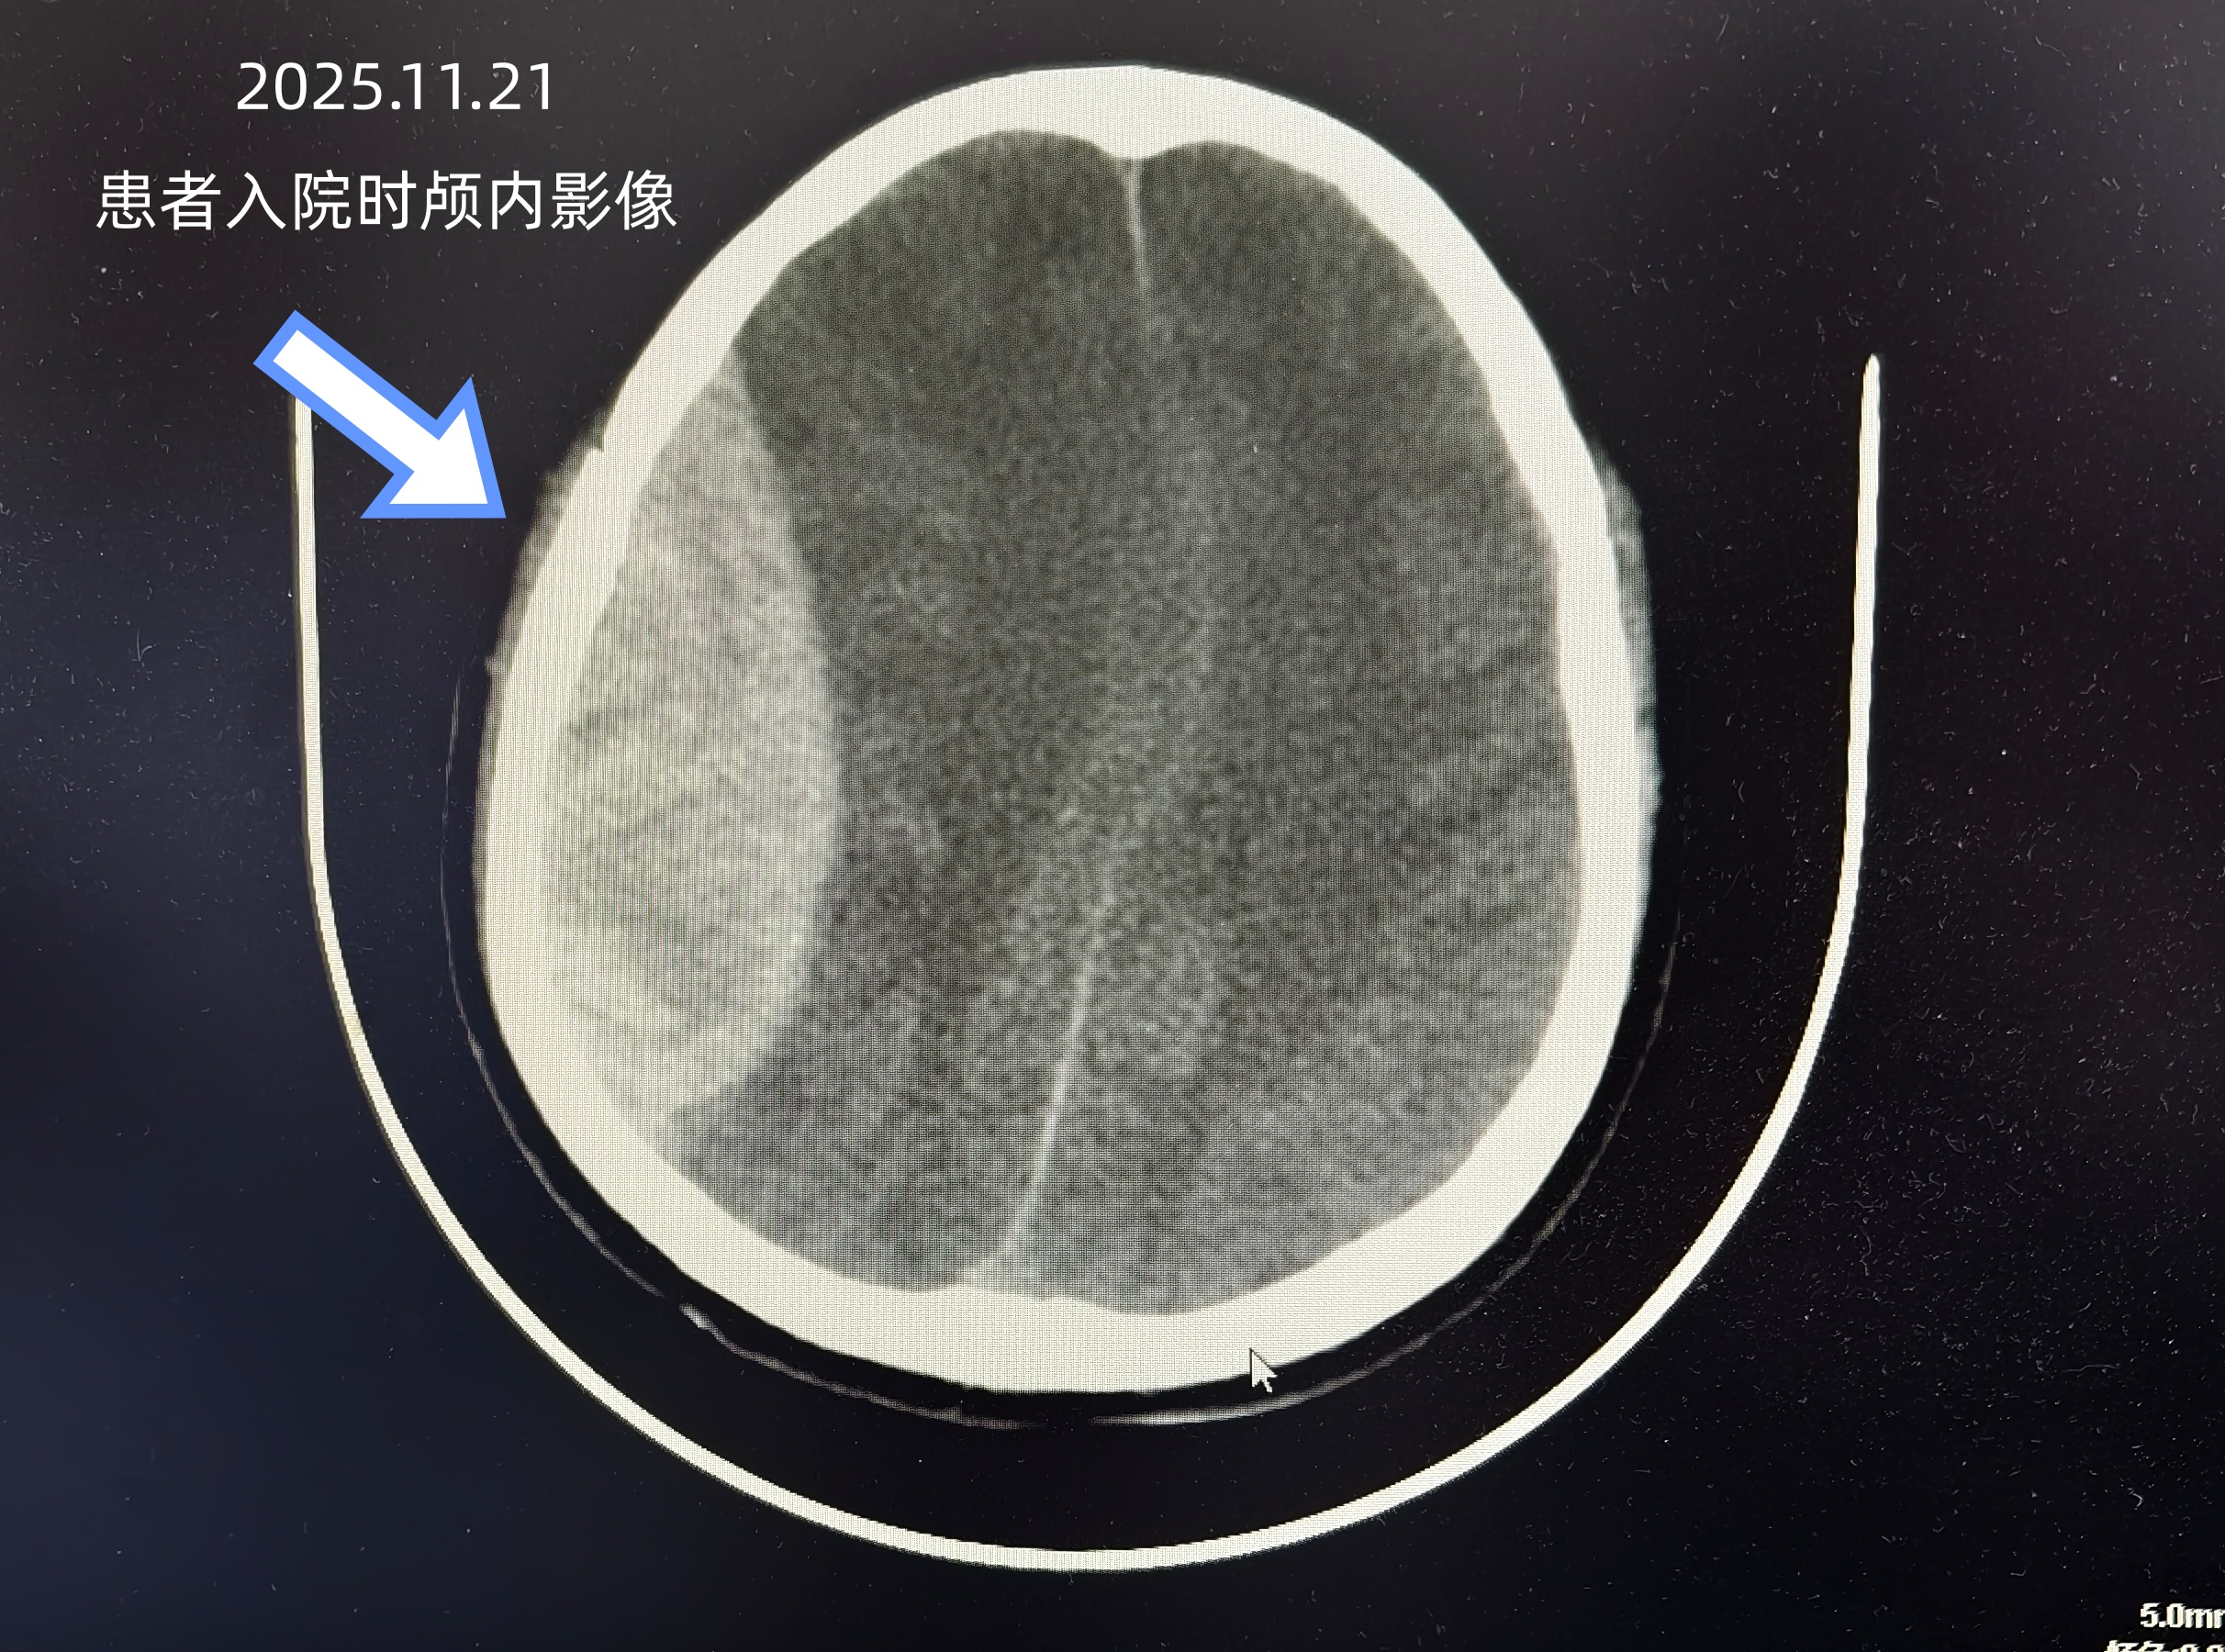

11月21日,叶某被3米高树枝砸伤头部昏迷入院。医院迅速开启绿色通道,影像检查提示患者右侧额颞顶硬膜外多发血肿伴颅骨骨折,需立即手术抢救。在麻醉科、手术室团队的紧密配合下,神经外科团队其施行了“右侧额颞顶开颅硬膜外多发血肿清除术+骨瓣还纳术”,清除了右侧颅内血肿并复位骨瓣。手术操作顺利,但在返回重症监护病房(ICU)后,患者并未出现预期的意识复苏迹象,这一异常细节引起了重症医学科与神经外科团队的高度警觉。